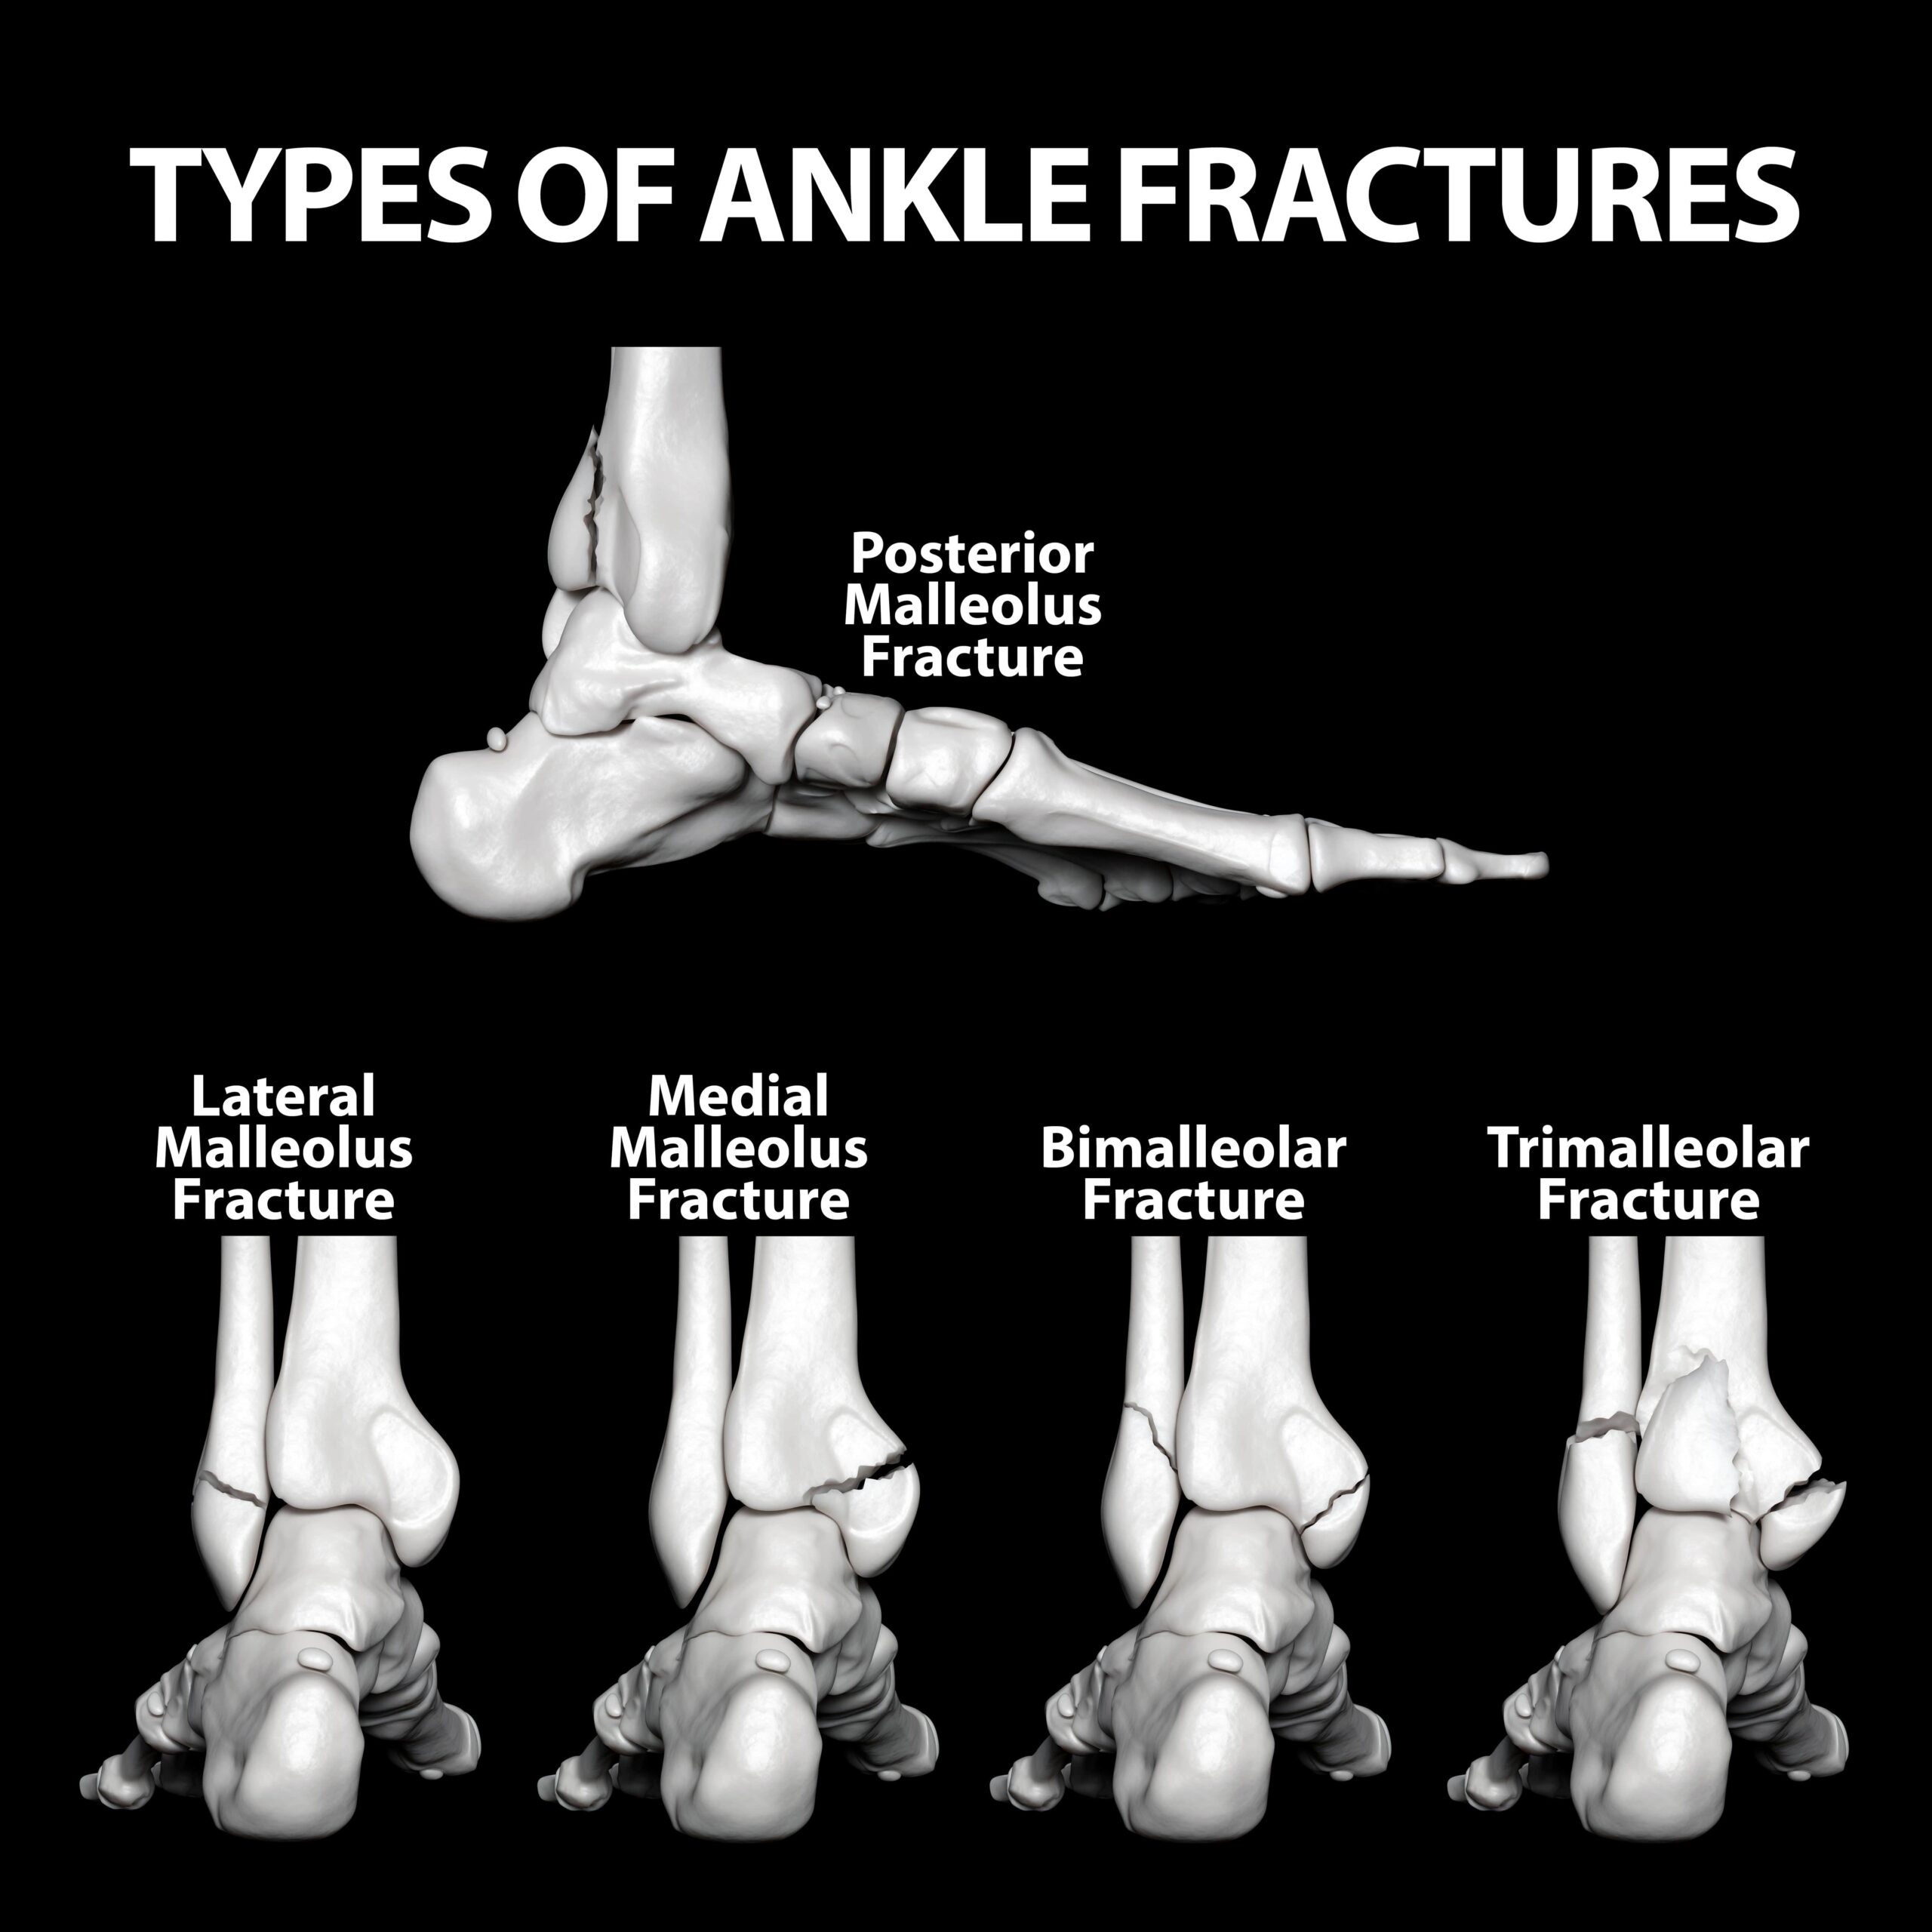

Ankle Fracture Repair Los Angeles | Broken Ankle Glendale | Pasadena

www.thomasharrismd.comankle fractures fracture stress sprain broken bone foot injury injuries small crack if know bursitis treatment worst overuse

www.thomasharrismd.comankle fractures fracture stress sprain broken bone foot injury injuries small crack if know bursitis treatment worst overuse

What Ankle Fracture Treatment Is Right For You? - Town Center Orthopaedics

X-ray Image Of Ankle Fracture , Broken Ankle , Pott Fracture Fix By

Ankle Fracture Surgery | Florida Orthopaedic Institute

www.floridaortho.comankle fracture surgery symptoms bones break

www.floridaortho.comankle fracture surgery symptoms bones break